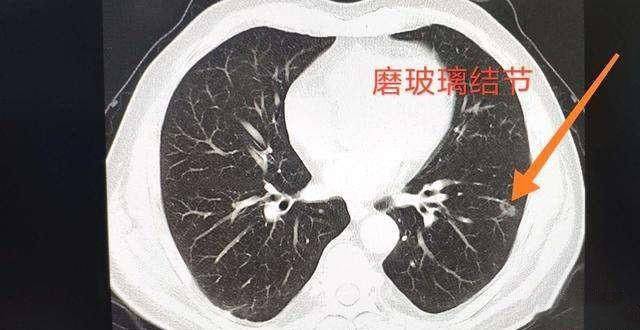

简单的说,就是你肺里长了一个东西,而且这个东西还会继续生长。如果这个时候你去做个肺部CT,就会显示出一团阴影,这团阴影被称为“磨玻璃结节”,这团阴影一般不大,在5mm左右。

要注意,虽然不典型腺瘤样增生表现为“磨玻璃结节”,但“磨玻璃结节”不一定是不典型腺瘤样增生,炎性肉芽肿、结核增殖灶、慢性炎症、局灶纤维化、炎症或出血等也可表现为“磨玻璃结节”,所以大家看到自己的报告单上写着“磨玻璃结节”也不要着急慌。